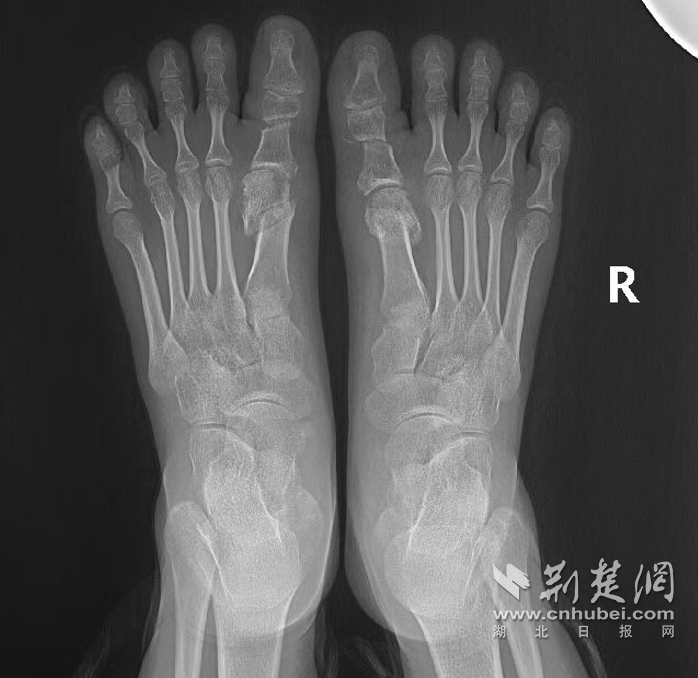

手术前。 通讯员 供图

术后6小时茜茜生活自理,独立完成如厕、洗漱、饮水等;术后24小时复查X线示截骨对位良好。在确保手术部位安全的前提下,王春玲指导其扶拐出院,并制定个性化康复计划,使其患肢通过科学、渐进的负重刺激,促进愈合,恢复功能,预防并发症。术后3个月随访,茜茜双足拇指功能接近正常,畸形矫正满意。

手术后。 通讯员 供图